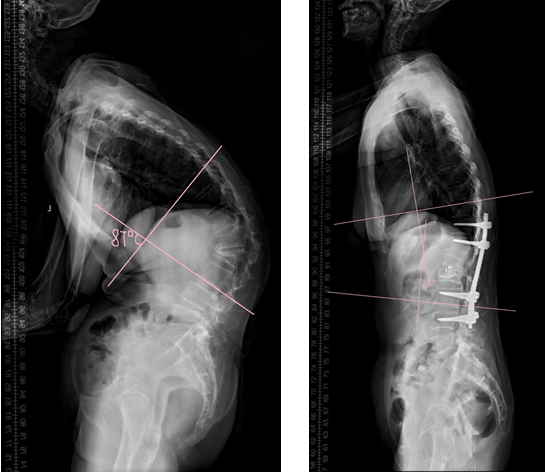

术前X线 术后X线

手术历经5小时,不仅是对手术医生的巨大考验,更是对团队技术、多学科协作的考验。麻醉科安排了经验丰富的麻醉医师和技术精湛的护理团队为本次手术保驾护航。输血科为该患者术前储存自体血300ml,术中采用自体血回收机,术中出血量450ml,术后回输自体血600ml。术后,Cobb角由术前的87°变为术后的15°,矫形效果满意,术后肢体功能良好。